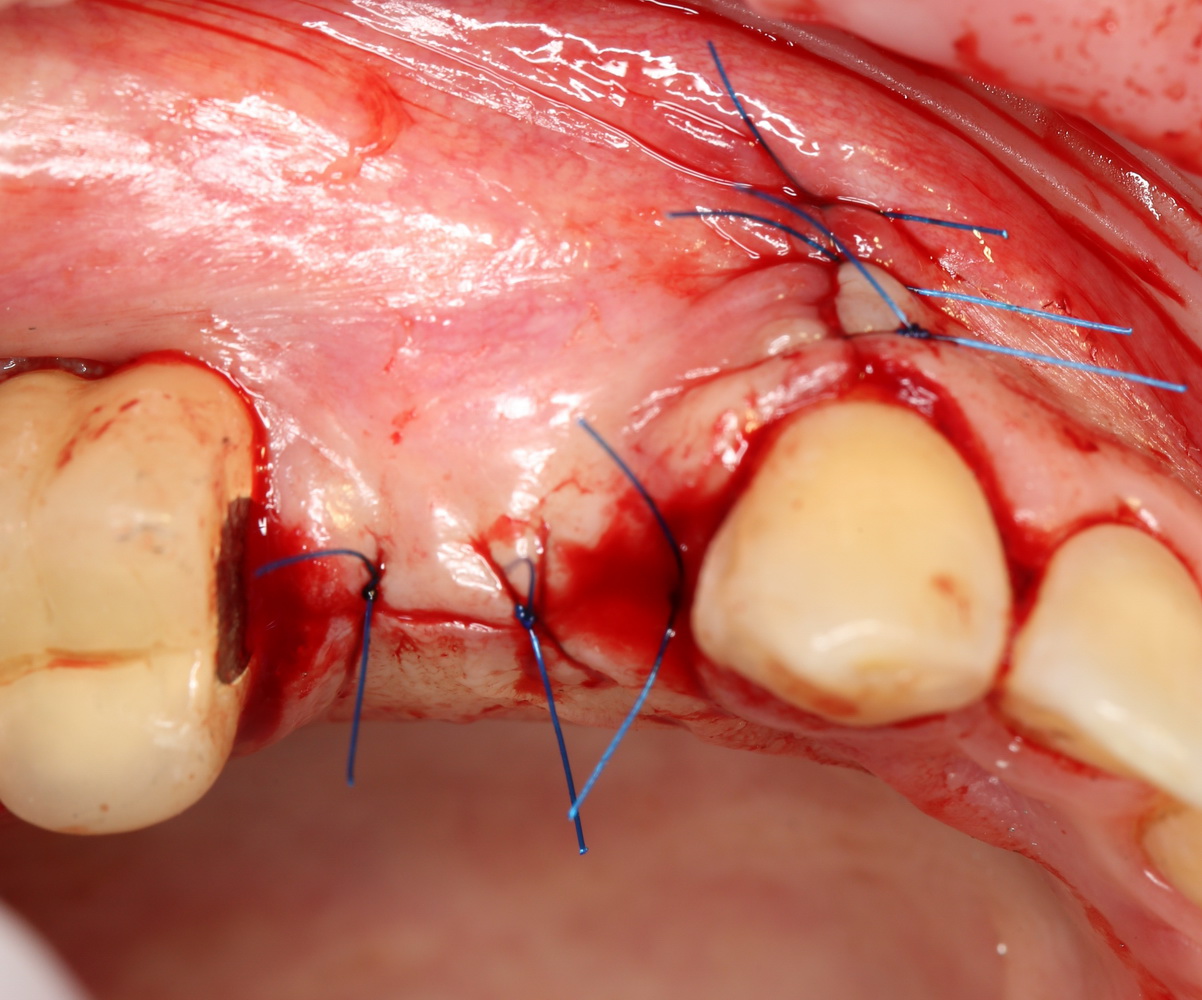

Накладываем швы:

Делаем назначения, даем рекомендации. И ждем.